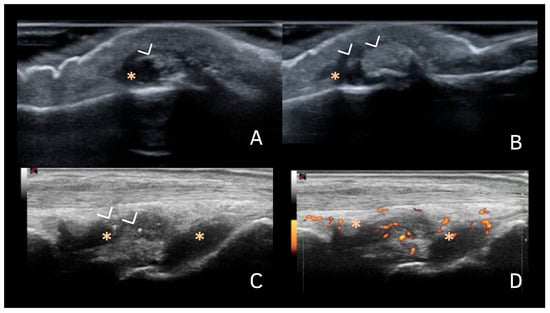

- Ruta, S.; Catay, E.; Marin, J.; Rosa, J.; García-Monaco, R.; Soriano, E.R. Knee effusion: Ultrasound as a useful tool for the detection of calcium pyrophosphate crystals. Clin. Rheumatol. 2016, 35, 1087–1091. [Google Scholar] [CrossRef]

| Synovial fluid | Shape: Deposits of variable shape and size. Echogenicity: Hyperechoic (similar to the bone cortex echogenicity), generally without posterior shadowing Localization: Within the synovial fluid. Dynamic scanning: Mobile according to joint movement and probe pressure. |